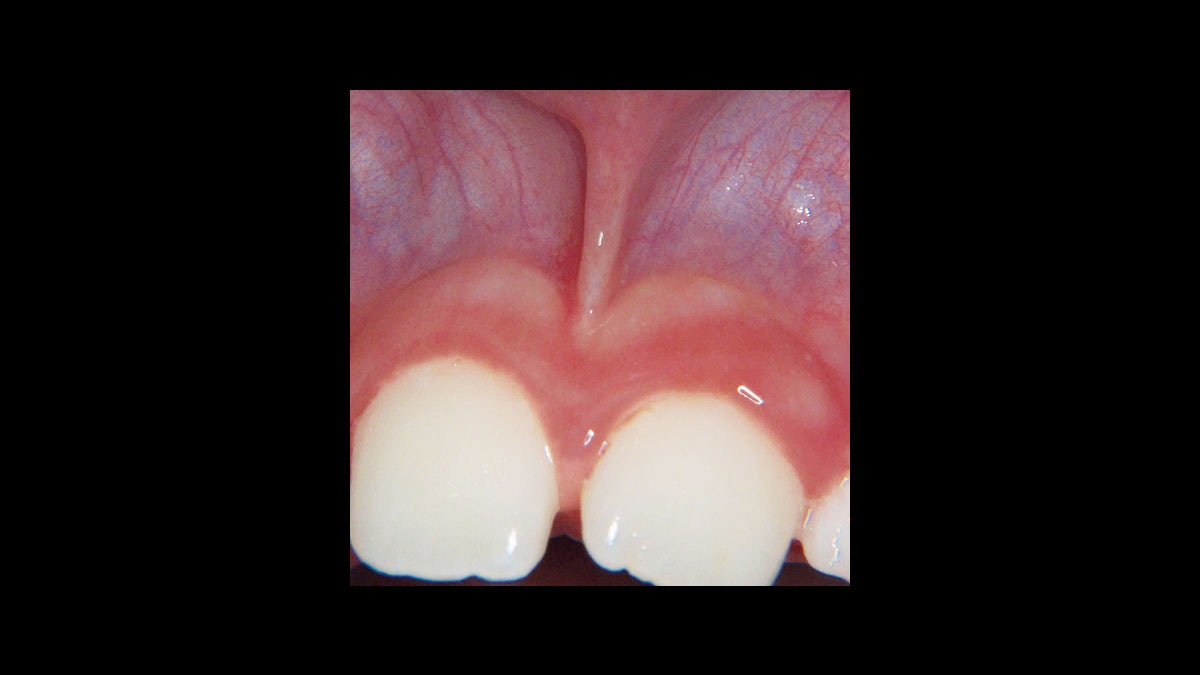

Frenectomy